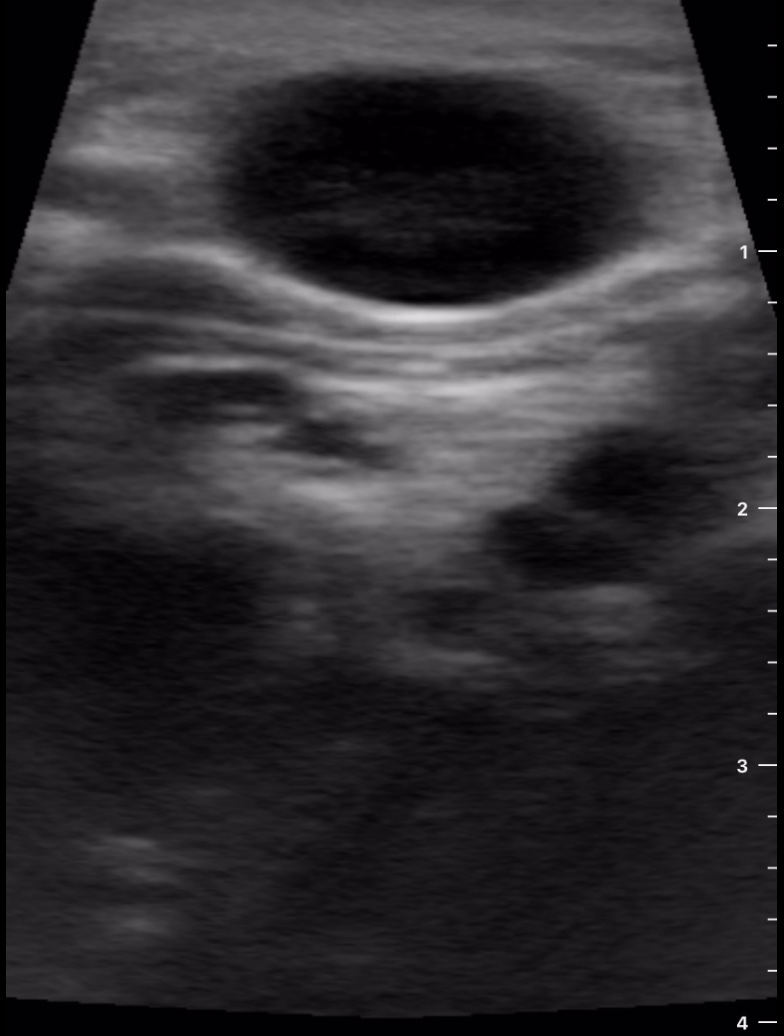

Se decide realizar ecografía clínica con ecógrafo de bolsillo para poder orientar caso, donde se aprecia tumoración de gran tamaño hipoecoica, heterogénea, con calcificaciones de pequeño tamaño en su interior, dependiente de lóbulo tiroideo derecho, sin poder definir límites inferiores, y sin poder localizar la vena cava inferior pero visualizando imagen de vena trombosada junto al istmo.

Ante la sospecha de cáncer de tiroides y la visualización de trombosis venosa que probablemente corresponda a vena cava inferior por la localización se deriva a Urgencias de Hospital de referencia, describiendo hallazgos y sospecha diagnóstica.